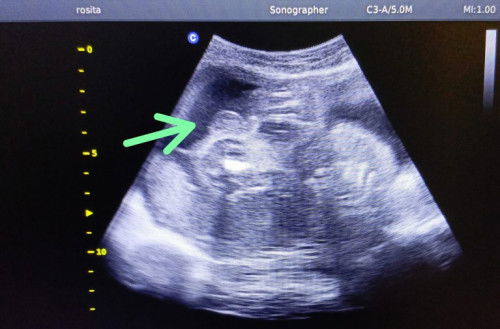

Jelas apa tidak

Assalamualaikum bunda² yang jk nya cowo/cewe ini keliatan jelas gk ya kira² tapi kata dokter si cowo kata kalian ini jls gk🤭takutnya nnti kena prank hhee